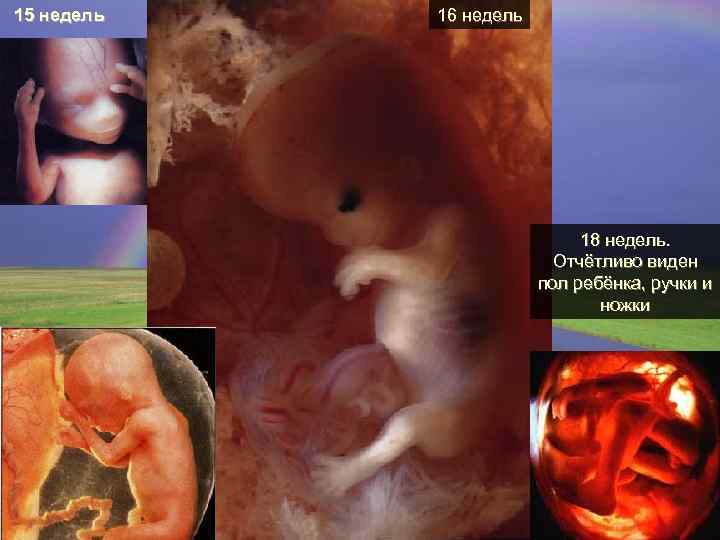

15 недель 16 недель 18 недель. Отчётливо виден пол ребёнка, ручки и ножки